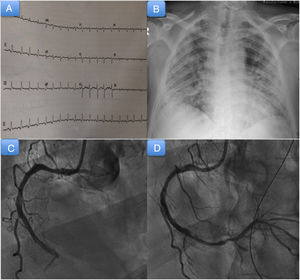

El electrocardiograma inicial (figura 1A) mostraba taquicardia sinusal con mínimo supradesnivel del ST aislada en III e infradesnivel del ST en V2-V4, que se corrigió en los electrocardiogramas sucesivos. En la radiografía de tórax (figura 1B) destacaba la presencia de infiltrados algodonosos globales de predominio periférico en ambos campos pulmonares, y la analítica inicial mostraba insuficiencia renal aguda (creatinina, 2mg/dl) y elevación enzimática significativa, con creatincinasa MB en 731 U/l y troponina T ultrasensible en 1.162 ng/l. Se documentaron valores elevados de interleucina 6 (135 pg/ml), ferritina (145μg/l), lactato deshidrogenasa (992 U/l), dímero D (55 mcg/ml) y fracción aminoterminal del propéptido natriurético cerebral (4.076 pg/ml).

En las siguientes horas, el paciente presentó deterioro hemodinámico franco, con posterior evolución a shock mixto, por lo que precisó inicio de soporte vasoactivo con noradrenalina hasta una dosis de 0,44mg/kg/min. Se realizó un cateterismo cardiaco urgente (figura 1C,D), en el que se observó enfermedad coronaria de 3 vasos con oclusión trombótica aguda de la coronaria derecha, que precisó angioplastia y el implante de 2 stents farmacoactivos, con migración de material trombótico hacia la descendente posterior.